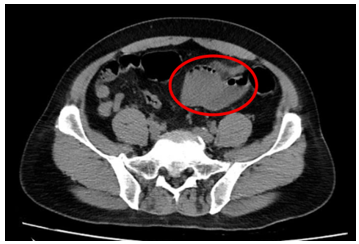

- Chụp cắt lớp vi tính ổ bụng(11/07/2025) – trước phẫu thuật:

Hình 1: Hình ảnh chụp cắt lớp vi tính ổ bụng: Quai hồi tràng vùng hạ vị dày thành không đều, tạo khối kích thước 49x47mm (vòng tròn đỏ), thâm nhiễm mỡ xung quanh, ngấm thuốc mạnh đồng nhất sau tiêm.